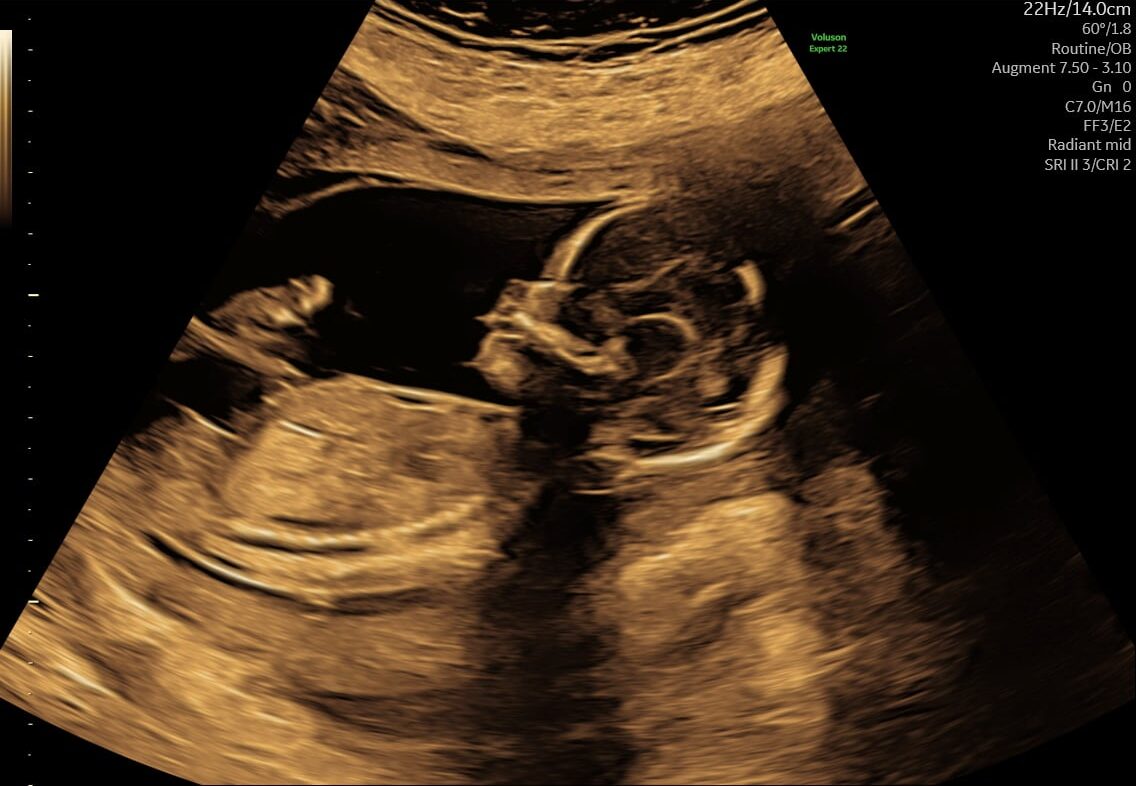

Ved en tryghedsscanning fra uge 14+0 vurderer vi blandt andet:

- hjerteaktivitet

- bevægelser

- fostervand

- moderkagens placering

- generel trivsel

Vi vurderer bl.a. hjerteaktivitet, bevægelse, fostervandsmængde, moderkagens placering og generelle trivselstegn.